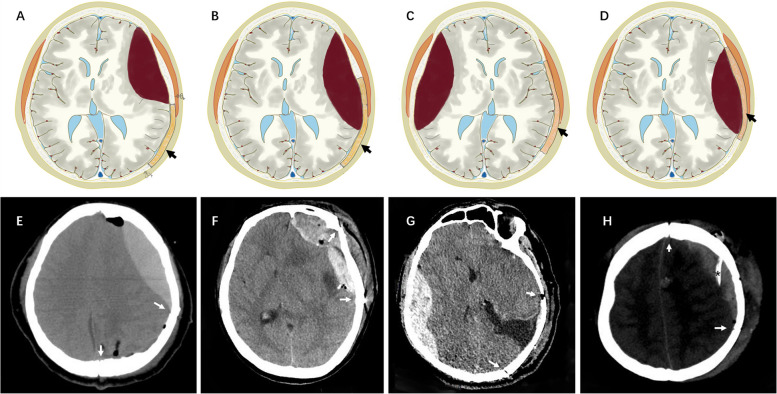

Results: Twenty-five patients (10 males, 15 females; median age 42 years, range 11-61 years; median medical history 27 months, range 1-96 months) were enrolled in the study. Regarding tumor location, 16 cases exhibited supratentorial brain tumors, 4 cases had infratentorial brain tumors, 2 cases of tumors occurred in the petroclival region, 2 cases in the peritorcular region, and 1 case in the pineal region. Four of these cases were complicated with supratentorial hydrocephalus. The 25 cases in this study were classified into four types based on location. Type 1 refers to EDHs that occur at the adjacent site of the operative field without involvement of the surgical area. Type 2 includes hematomas that occur at the adjacent site of the surgical area and the surgical area. Type 3 includes EDHs that occur in distant areas, and type 4 involves EDHs in the surgical field. The numbers of cases of types 1, 2, 3, and 4 PEDHs were 16, 2, 3, and 4 cases, respectively. Most PEDHs were associated with reduced ICP after craniotomy due to intracranial tumor resection and substantial loss of CSF. All patients achieved satisfactory outcomes after hematoma evacuation.